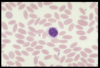

Name this WBC

Neutrophil